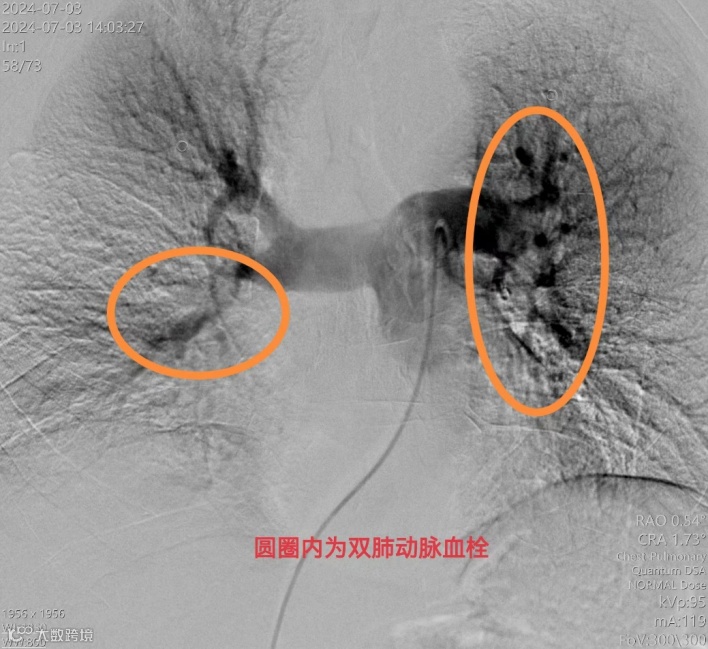

手术过程